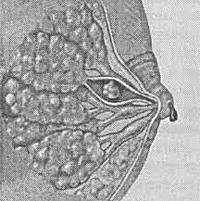

Внутрипротоковая папиллома молочной железы выглядит как выступающее в просвете протока или кистозной полости сосочковидное разрастание, иногда напоминающее по форме цветную капусту.

Макроскопически внутрипротоковая папиллома молочной железы напоминает кистозное образование с сосчковидными разрастаниями. Папилломы легко травмируются, а выделяющаяся при этом кровянистая жидкость попадает в выводные протоки и выделяется наружу из соска. В области опухоли возможны кровоизлияния и некрозы; озлокачествлению чаще подвергаются множественные внутрипротоковые папилломы молочной железы.